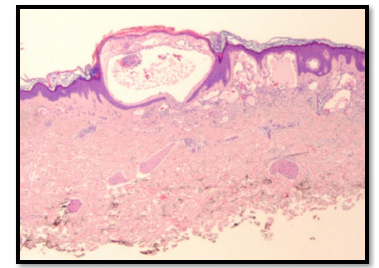

Figure 3:Histopathologic examination showing Lymphangioma Circumsciptum (Case 1).

An atypical aspect in the second case was the occurrence of Iron Deficiency Anemia (IDA), which is not typically linked with LC but may arise from chronic, low-grade blood loss due to vesicle rupture or ongoing oozing over time [15]. Although instances of IDA secondary to LC are uncommon, a comparable case was reported by Bittencourt et al. underscoring the necessity for clinicians to monitor hemoglobin levels in patients with bleeding-prone LC [16]. An unusual aspect in the second instance was the occurrence of Iron Deficiency Anemia (IDA), which is not typically linked with Lymphatic Malformation (LC) but may arise from chronic, lowgrade blood loss due to vesicle rupture or ongoing oozing overtime [17]. Although instances of IDA secondary to LC are infrequent, a comparable case was reported by Bittencourt et al. underscoring the necessity for clinicians to monitor hemoglobin levels in patients with bleeding-prone LC [18]. From a pathophysiological perspective, LC is regarded as a microcystic lymphatic malformation resulting from the sequestration of lymphatic tissue during embryonic development, leading to clusters of dilated lymphatic channels that connect with the superficial dermis [19]. Histologically, it is defined by thin walled, dilated lymphatic spaces lined by a single layer of endothelial cells, which may sometimes extend into the epidermis [8]. Although histopathological confirmation was not achieved in our cases due to the typical clinical features, it remains the diagnostic gold standard when the presentation is atypical.